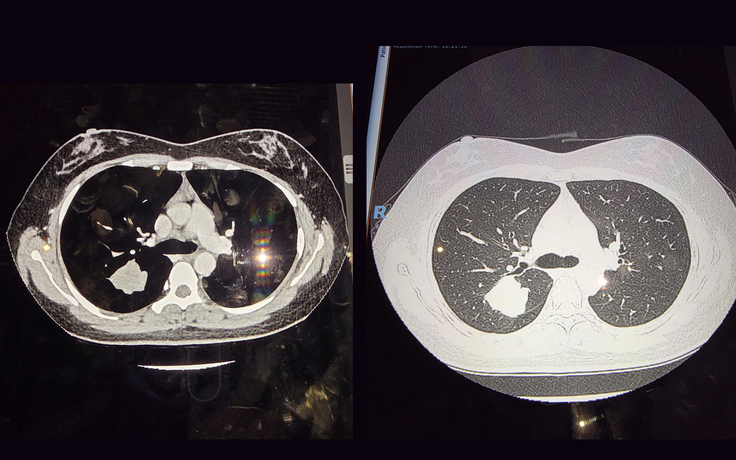

‘Mắt thần’ trong tầm soát ung thư phổi: Một nốt mờ nhỏ thay đổi tiên lượng sống

Theo ghi nhận lâm sàng, không ít trường hợp người bệnh ngoài 50 tuổi, không có triệu chứng, chỉ phát hiện một 'nốt mờ' nhỏ trong phổi khi khám sức khỏe định kỳ. Sau một thời gian theo dõi, nốt này có thể tăng kích thước và được xác định là ung thư phổi giai đoạn sớm.